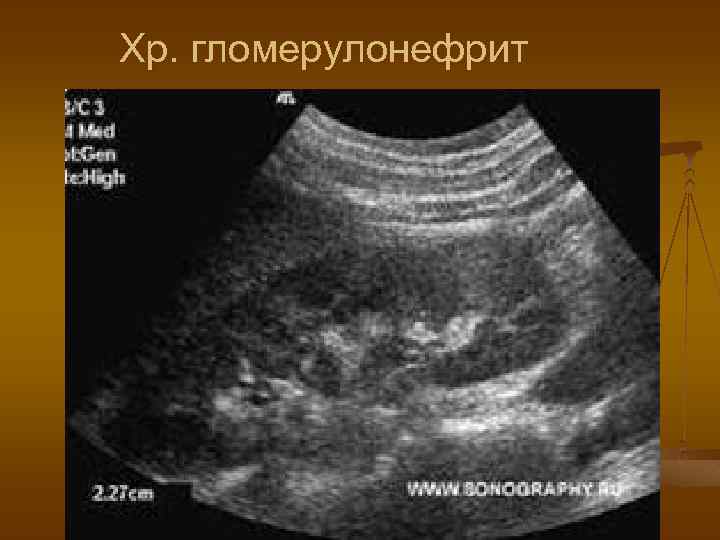

УЗ признаки хр. гломерулонефрита n n n Проргрессирующее уменьшение размеров почки Повышение эхогенности паренхимы Потеря кортикомедуллярной дифференцировки Обеднение сосудистого рисунка в кортикальном слое Вторичносморщенная почка

Хр. гломерулонефрит